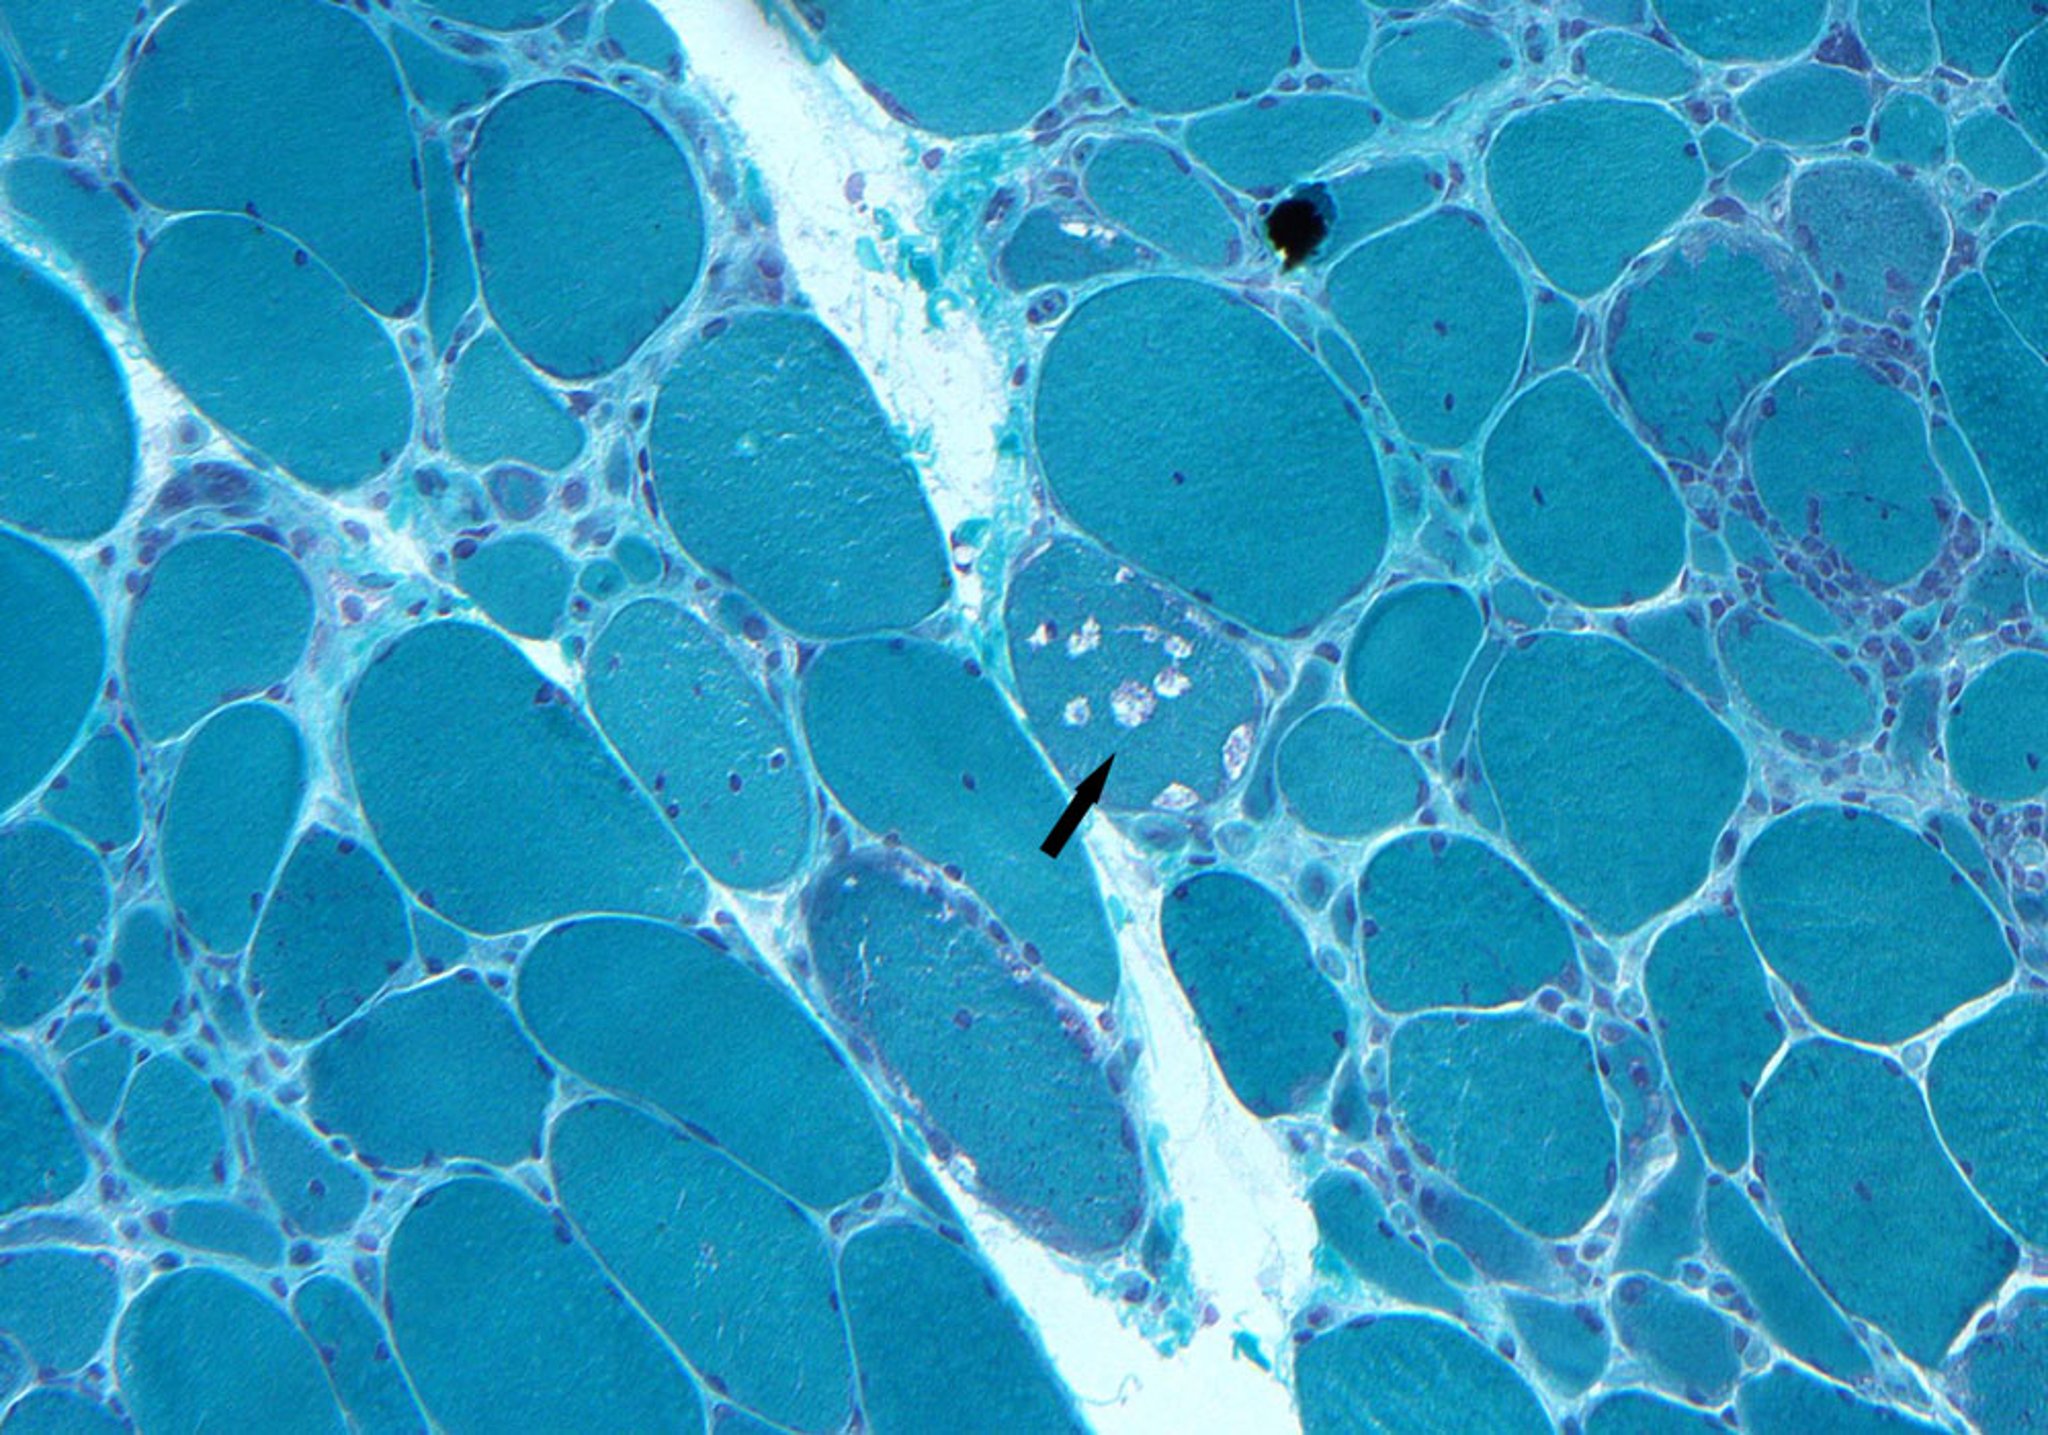

Inclusion Body Myositis

This biopsy specimen shows endomysial infiltrates, myofiber degeneration, and rimmed vacuoles (arrow).